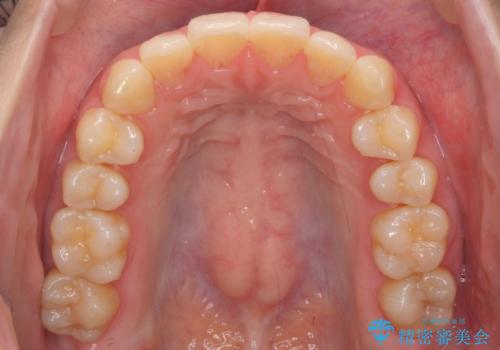

- 前歯のがたつきをきにされていました。

上下の前歯をやすりがけする処置(IPR)を行い、前歯の並びを出っ歯にしないようにしながら整えました。

症状が軽度であるためモニター採用になりました。